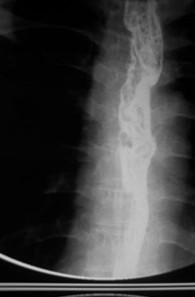

女,51歲,以“進(jìn)行性吞咽困難1年”為主訴于2007年2月19日入院。鋇餐造影、胃鏡示食管上段占位性病變,確診為食道鱗癌(圖1),拒絕手術(shù),行放療+今又生治療。食道鏡下瘤內(nèi)注射今又生,1×1012VP/次/周×6,放療在今又生注射3 d后開始,采用常規(guī)分割三野等中心照射,劑量65cGY。治療結(jié)束后4周,食管X線、胸部CT顯示腫瘤完全消退(圖4-5)。

放療40GY+今又生4支后